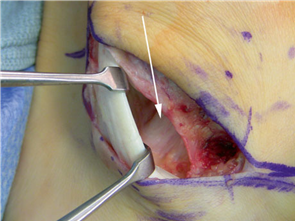

The Lapidus Arthrodesis (First TMT Fusion)

For severe deformities or hypermobility, the Lapidus procedure provides robust stabilization of the medial column. A dorsal or medial incision is utilized over the first TMT joint. The extensor hallucis longus (EHL) is retracted dorsally, and the tibialis anterior tendon is identified and protected at its insertion on the medial cuneiform and first metatarsal base. The TMT joint capsule is incised, and the joint is thoroughly debrided of all articular cartilage using a combination of osteotomes, curettes, and a high-speed burr.

To achieve multiplanar correction, the surgeon must address the sagittal, coronal, and transverse planes. The first metatarsal is plantarflexed to restore the longitudinal arch, rotated out of pronation to realign the sesamoids, and translated laterally to close the IMA. Subchondral drilling or feathering is performed to optimize the biological environment for fusion. Fixation is traditionally achieved with two or three crossed solid or cannulated screws (typically 3.5mm or 4.0mm). Recently, plantar or medial locking plates have gained immense popularity due to their superior biomechanical construct, allowing for earlier weight-bearing. Bone graft or orthobiologics may be packed into the arthrodesis site to stimulate osteogenesis.

Clinical & Radiographic Imaging Archive